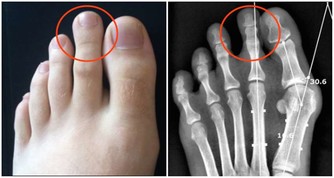

5. 頸椎退化或骨刺

隨著年齡增長,頸椎可能會出現退化或骨刺問題,影響神經與肌肉運作,導致慢性肩頸疼痛。這類問題通常伴隨手部麻木、頭暈等症狀,建議盡早就醫檢查。